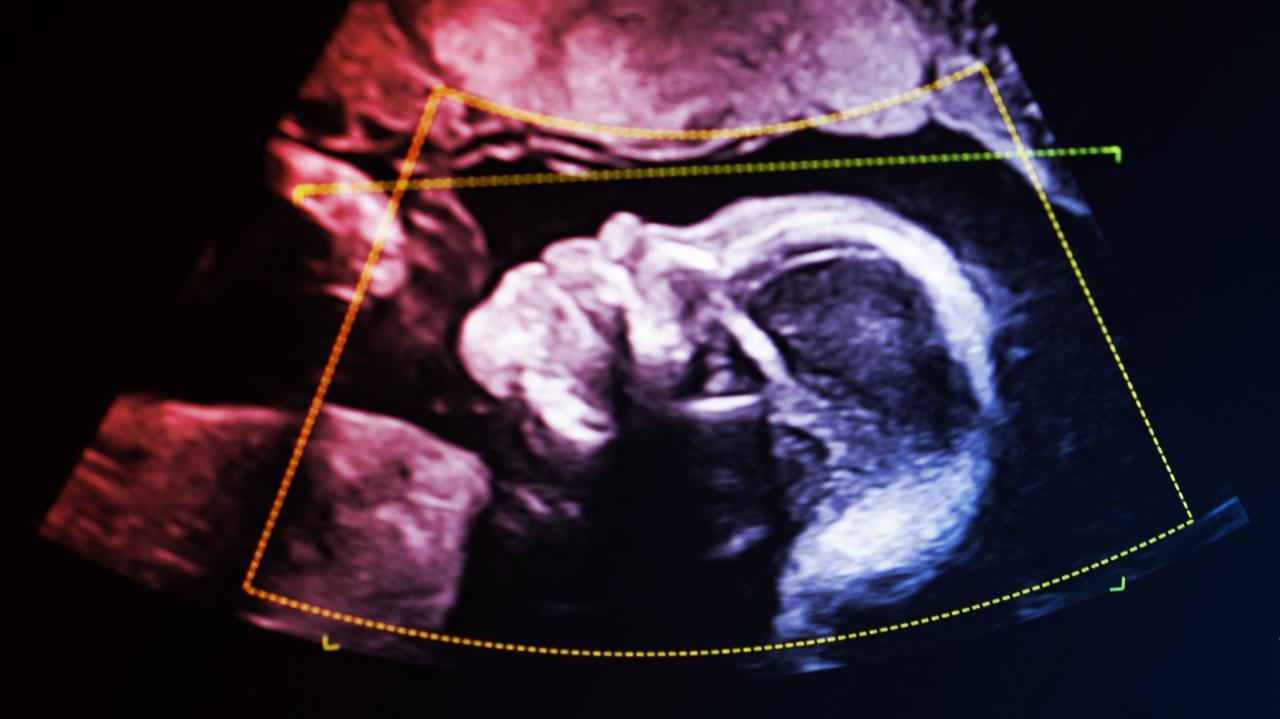

Az egész ügyet még nyomasztóbbá tette, hogy épp harmadik gyermekét várta, a bíróság pedig azonnali vizsgálatot rendelt el a születés után. A döbbenet csak fokozódott, mert a legkisebb újszülött sem tartozott hozzá genetikailag – legalábbis laboratóriumi értelemben.